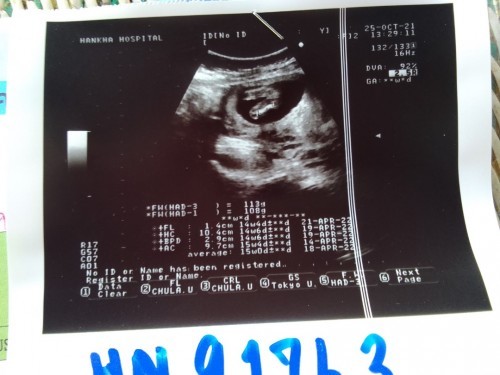

เจอตอน 6 วีคค่ะ

8วีคค่ะคุณแม่

บ้านนี้8weekค่ะ